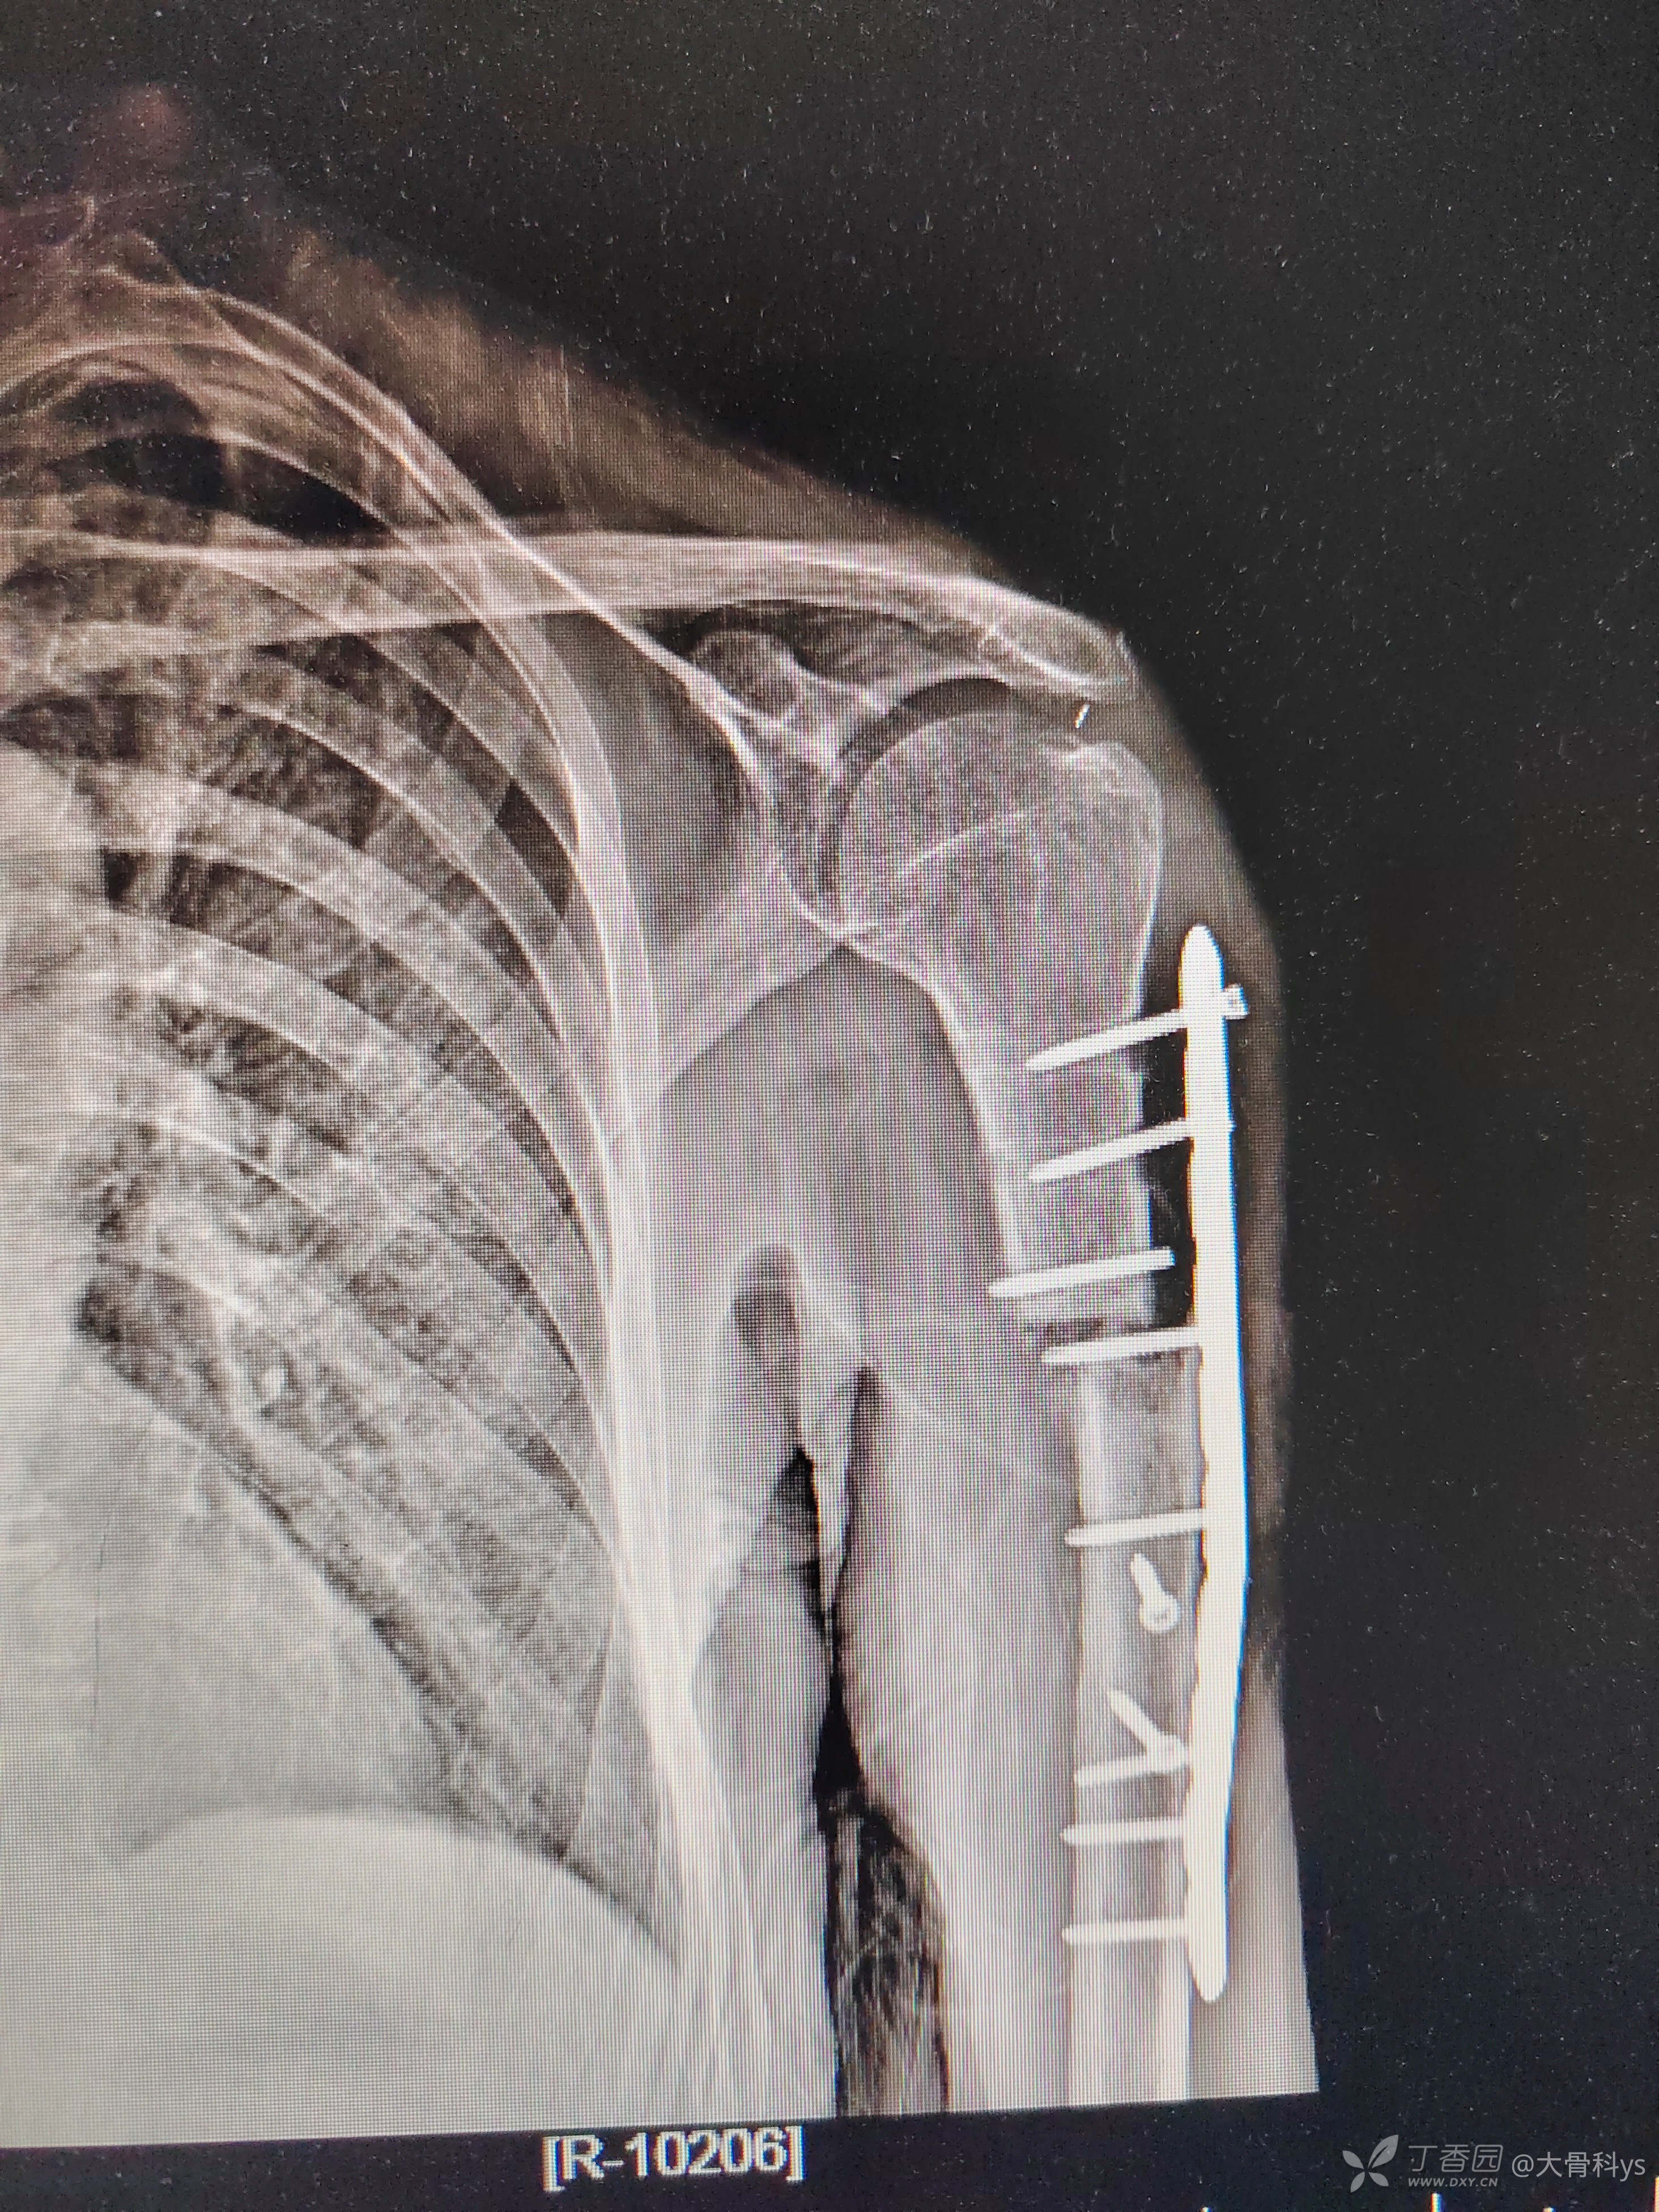

81岁男性患者,2年前在我院兄弟科室手术,术前影像学资料未查阅到,术后照片如下